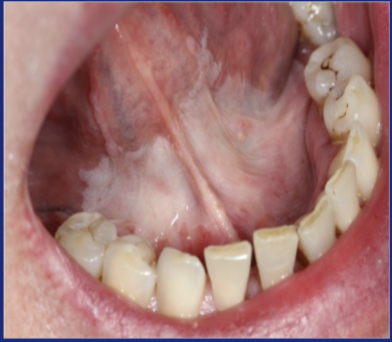

Occlusal line Hyperplastic lesion

What is this?